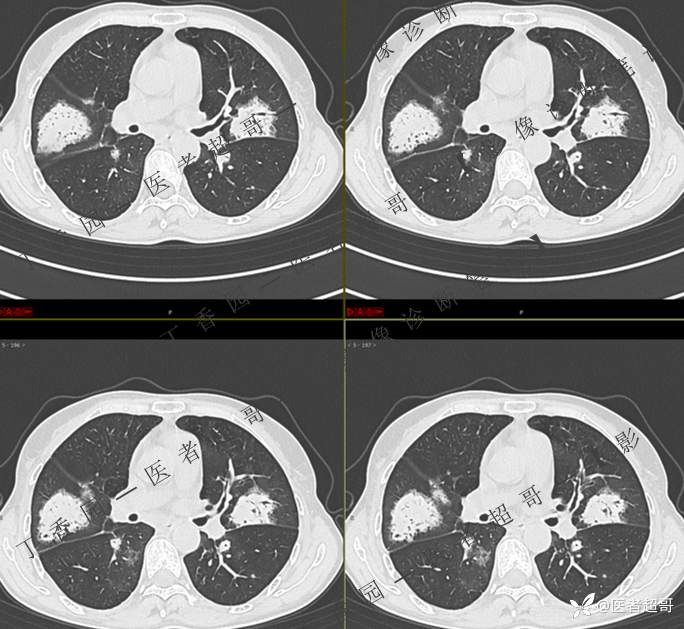

2402胸部影像病例︱持续追踪的一个患者,时间轴较长,闭卷分析,请畅所欲言~~~

女性,57岁

临床治疗一周后复查